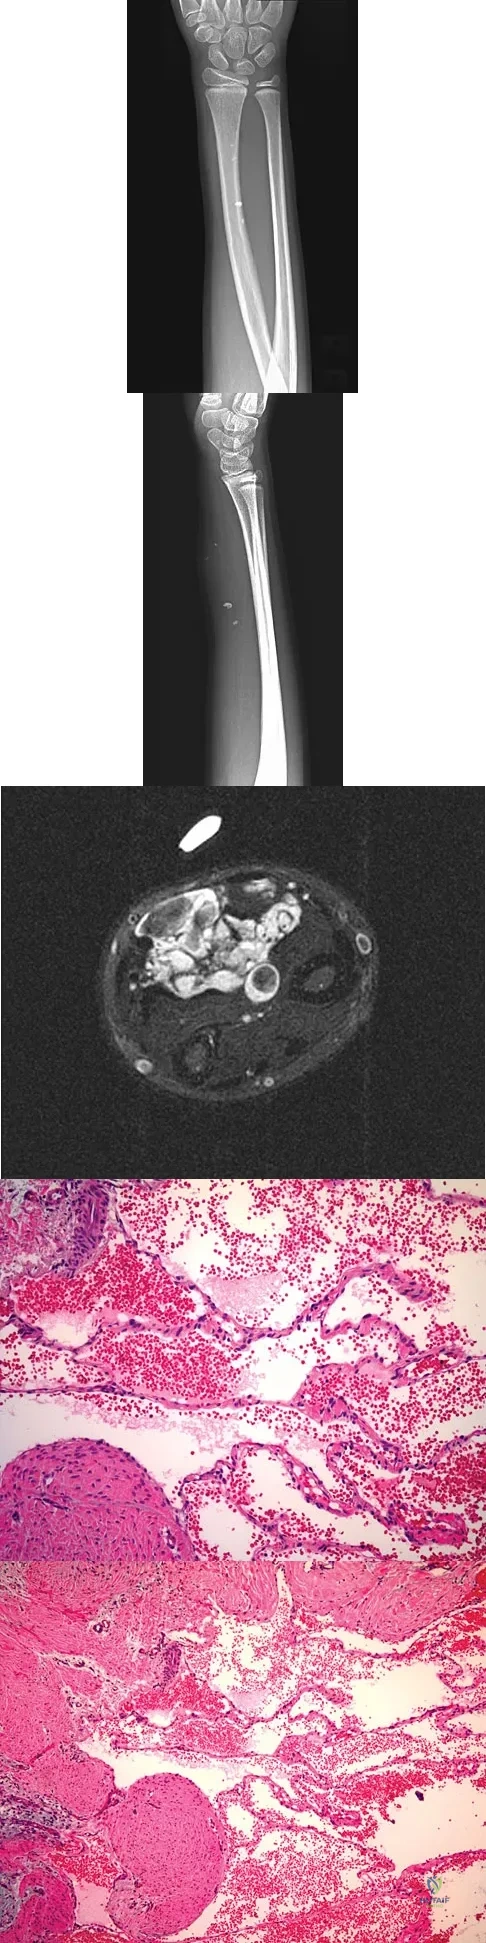

A 23-year-old man has had right posterolateral knee pain and occasional lateral calf dysesthesias for the past 8 months. A radiograph, CT scan, MRI scans, and a biopsy specimen are shown in Figures 62a through 62e. What is the most likely diagnosis?

Explanation:

The radiograph shows an eccentric, cortically based lytic lesion in the proximal fibula. The CT and MRI scans confirm that it is well circumscribed and cortically based with significant surrounding edema. The radiographic differential diagnosis would be a Brodie's abscess or osteoid osteoma. An osteoblastoma would have to be greater than 2 cm in size. A chondroblastoma may also have significant edema around it, but it is an epiphyseal-based lesion, not cortically based. The well-circumscribed nature of the lesion is not consistent with osteosarcoma. The pathology shows a very cellular and vascular stroma with plump, but not atypical osteoblast cells making a matrix of immature woven bone. There are no abundant inflammatory cells or dead bone suggestive of osteomyelitis or a Brodie's abscess. Therefore, the clinical and histologic picture is most consistent with an osteoid osteoma. Percutaneous radiofrequency ablation, usually with CT guidance, has become the preferred method for treating most cases of osteoid osteoma. Rosenthal DI: Radiofrequency treatment. Orthop Clin North Am 2006;37:475-484.